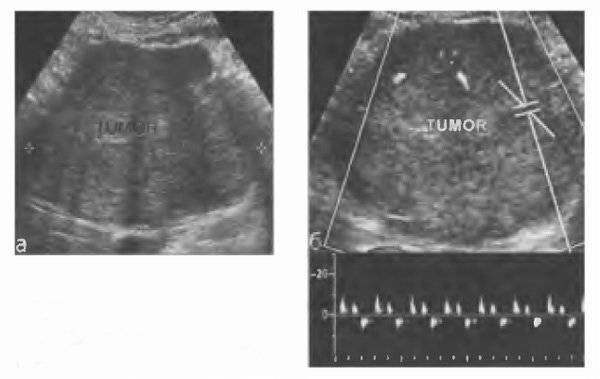

Диагностика При УЗИ узловая гипертрофия печени визуализируется в виде солитарных образований с однородной, изо- или незначительно гипоэхогенной структурой округлой формы с ровным контуром. В ряде случаев выявляется «центральный рубец». Типичен гиперваскулярный характер опухоли, что заставляет проводить дифференциальный диагноз со злокачественными опухолями. Основной дифференциально- диагностический критерий по данным цветового дуплексного сканирования — наличие спектра печёночных вен в структуре фокальной нодулярной гиперплазии (рис. 59-4).

Рис. 59-5. Компьютерная томограмма (артериальная фаза контрастирования): фокальная нодулярная гиперплазия правой доли печени.